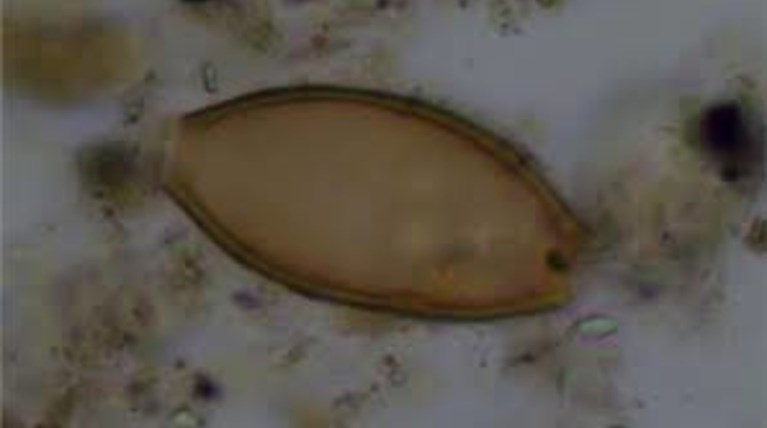

Η μελέτη αποκάλυψε σε τέσσερις από τους 25 σκελετούς (ποσοστό 16%) ότι μέσα στα αρχαία κόπρανα υπήρχαν υπήρχαν αυγά από δύο είδη εντερικών παρασιτικών σκωλήκων (έλμινθες): την ασκαρίδα (Ascaris lumbricoides) μήκους έως 30 εκατοστών και την τριχουρίδα (Trichuris trichiura) μήκους τριών έως πέντε εκατοστών. Το πρώτο παράσιτο βρέθηκε σε δείγματα από την εποχή του Χαλκού και μετά, ενώ το δεύτερο από τη νεολιθική εποχή και μετά.

Οι ερευνητές θεωρούν ότι η έρευνά τους έφερε στο φως μερικά από αυτά τα είδη των ιπποκρατικών παρασίτων. Πιστεύουν ότι η ασκαρίδα που βρέθηκε στην Κέα, είναι το ίδιο παράσιτο που περιγράφεται στα αρχαία ιατρικά κείμενα ως έλμινθα στρογγυλή.